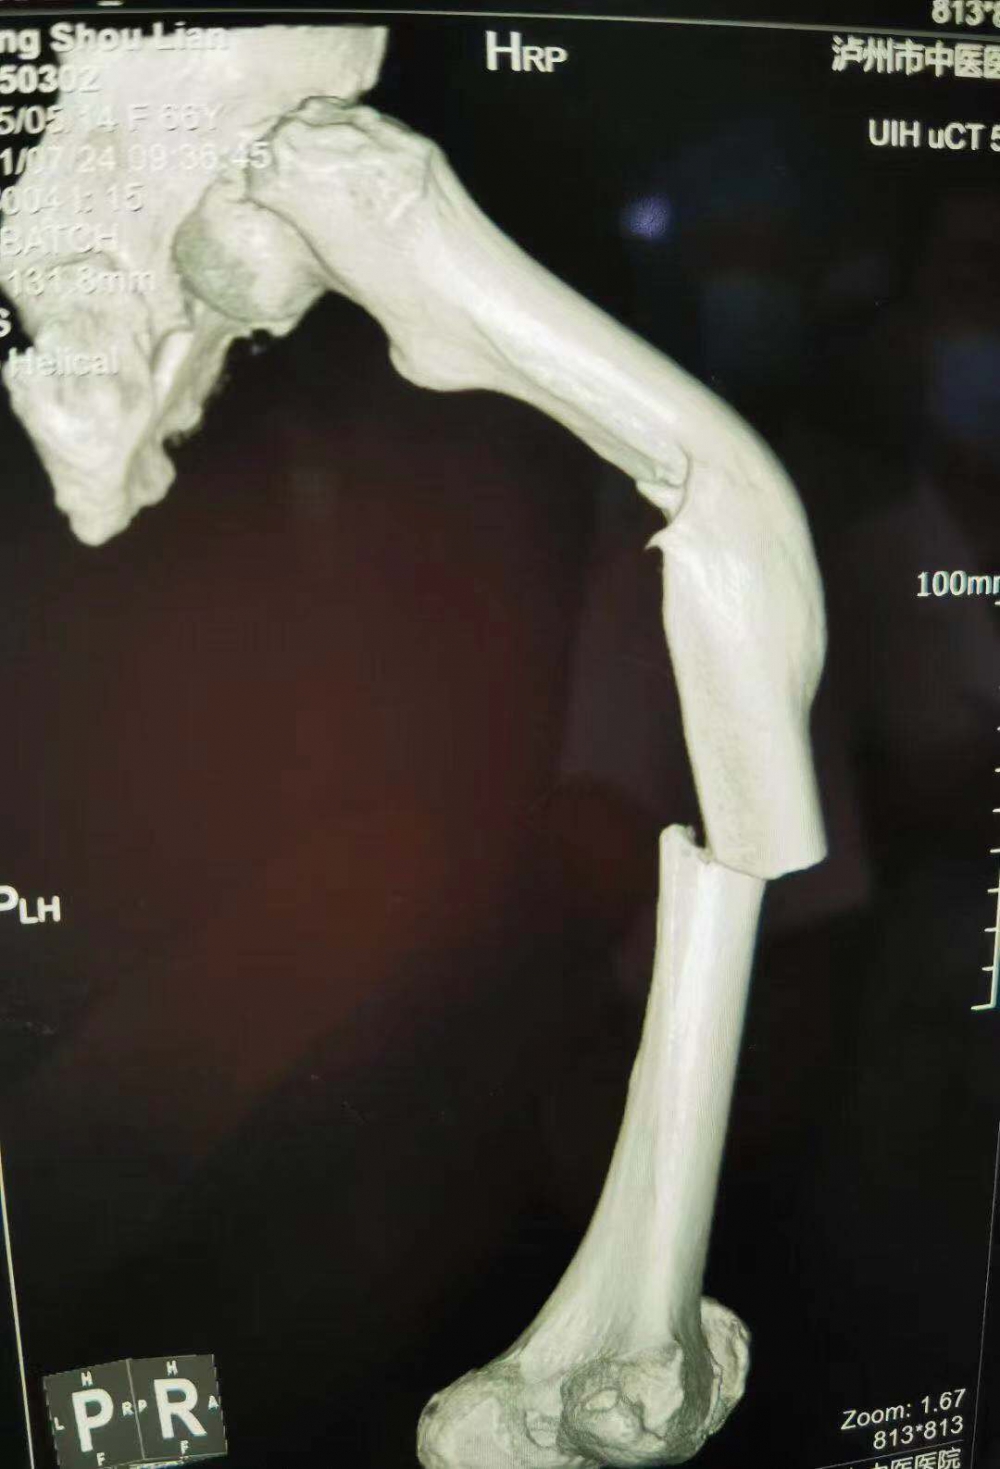

(股骨中段斷裂,上端有明顯畸形)

當她的X光片出來時,收治的醫(yī)生都被她的傷情嚇了一跳。原來此次她骨折的上端還有一處骨傷畸形愈合。這是什么情況呢?

原來張守蓮在三年前還摔傷過一次,當時在一家醫(yī)院進行了手法復位,但因操作不當,沒能復位成功,留下了后遺癥。三年來她都是以拄拐行走。

據(jù)瀘州市中醫(yī)院骨傷一科主任汪永泉介紹張女士的病情較為復雜,三年的時間導致神經(jīng)組織、血管等都已經(jīng)適應(yīng)畸形以后的狀態(tài)。